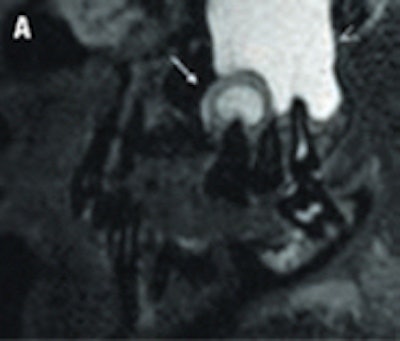

Imaging in these patients is usually performed with 2D panoramic radiography, CT, or CBCT. However, MRI may represent a complementary imaging technique to visualize particular pathological processes, especially inflammatory disease of the periodontal space, or teeth vascularization after trauma, he said. His presentation focused on the potential of high-resolution MRI in this new field and compared it with CT and CBCT.

"MRI of the dental apparatus is technically challenging as the bony structures of the mandible and teeth give only little or no MR signal," Rohde said. "Another concern is the problem of air content and metal artifacts in the oral cavity that limit the use of MRI in this special setting. As a principal finding of our experiments, MRI proved to be superior to MDCT [multidetector-row CT] and to CBCT in visualizing periodontal structures like the periodontal space and the adjacent lamina dura. Surprisingly, even cortical and trabecular bone were displayed better with MRI than with MDCT and CBCT. Therefore, I believe that MRI could become an important complementary imaging source of the jaw and teeth apparatus in pathologies of tissue investing and supporting the teeth."

An example of cone-beam CT. In this instance, the lower left third molar (d. 38) was imaged after panoramic radiograph with CBCT. The arrows mark the mandibular canal. Images courtesy of Dr. Anni Suomalainen.